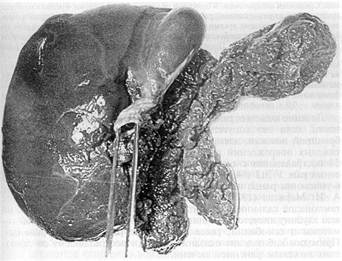

Рис 11 Печень погибшего во время операции больного С , 34 года (21 05 79 г) размозженная правая доля печени, левая — оторвана, виден полный поперечный разрыв воротной вены, в просвет которой введен пинцет